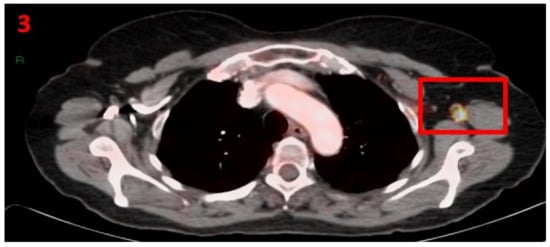

3.1. Case No 1

| Case no.1 | Breast cancer | Right arm | 5 days | Hypermetabolic uptake in the right axillary region and lymphadenopathy | First vaccine | 10 mm | 4.6 | Pfizer-BioNTech |